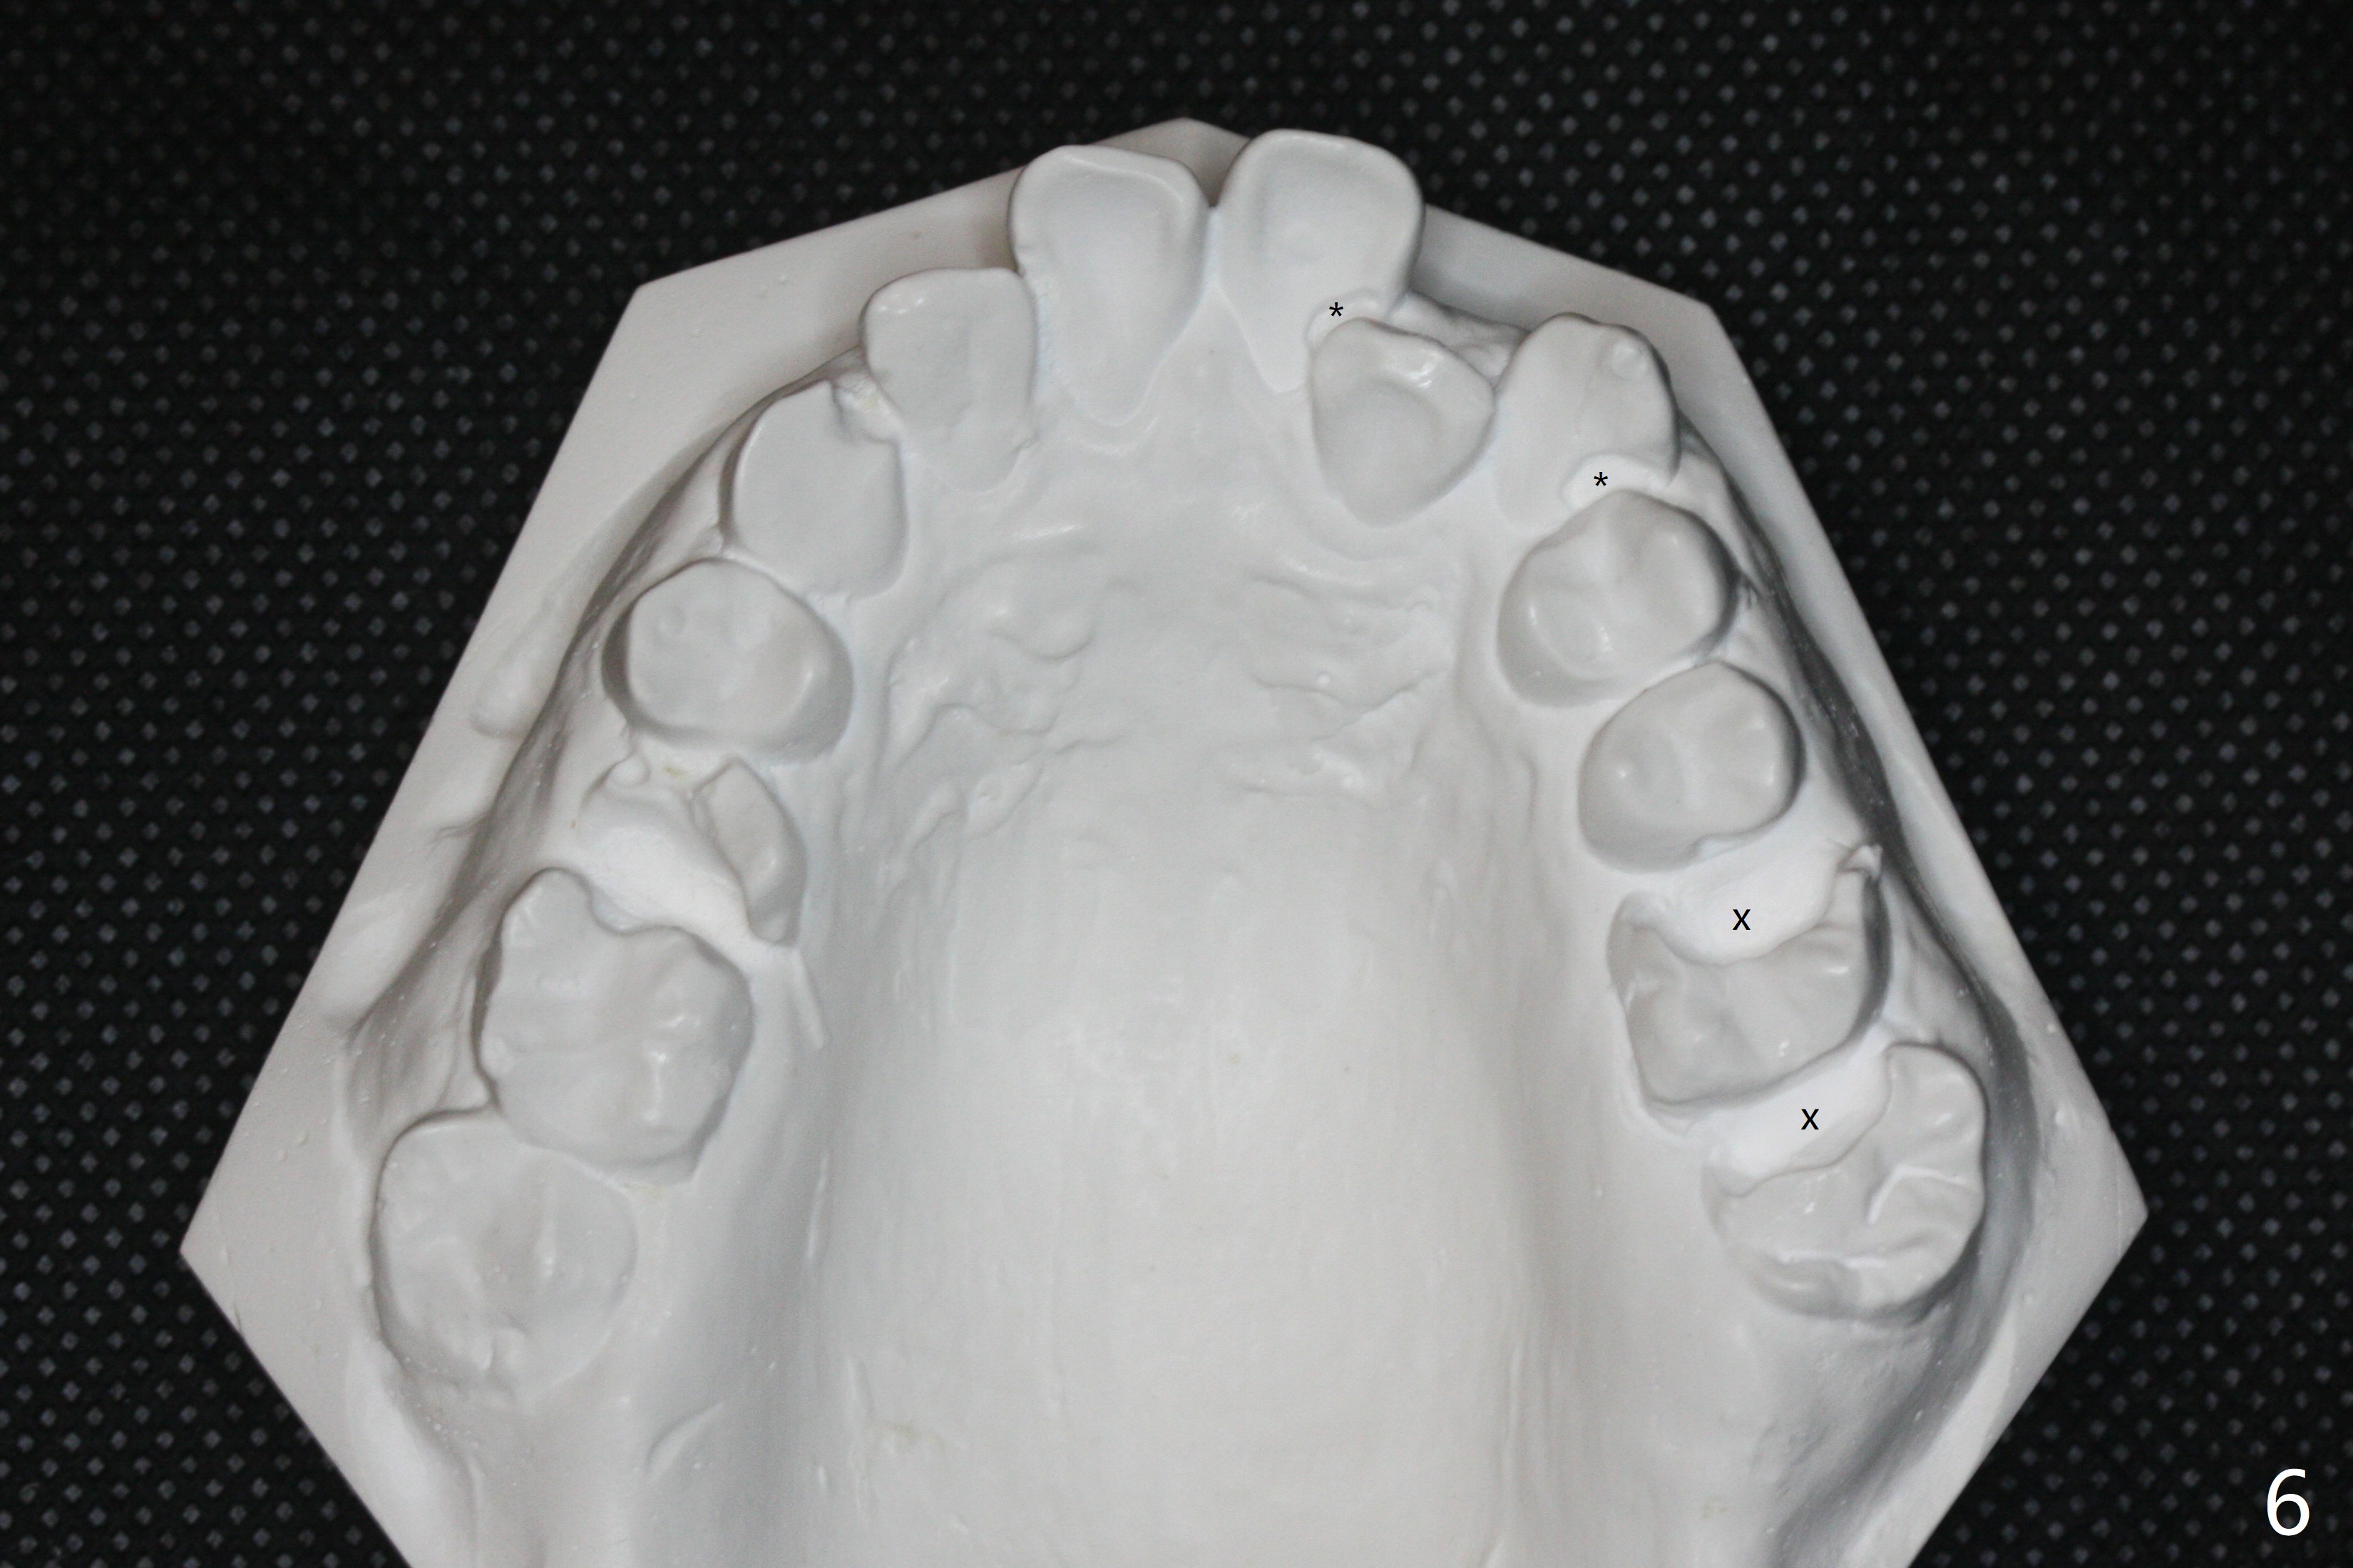

A 32-year-old man has had severe crowding for the last 10 years (Fig.1-5).  He is ready for orthodontic treatment now.  LL5 has been extracted for 4 years (Fig.1 x).  Severe caries at UR5 makes it easy to decide for extraction (Fig.2 x), while it is hard to determine which of the LR bicuspids needs to be extracted because of moderate caries at LR5 and even harder for UL because of caries at UL6,7 (Fig.2 *).

In fact impression for models (Fig.3-7) is taken after UL caries control.  Sedative filling is done at UL1,3 (Fig.6 *) and definitive restoration will be done when crowding resolves.  The defects at UL6,7 (Fig.6 x) is so extensive that after composite molar bands are placed immediately for retention.  Amazingly, there is no symptom after UL6,7 restoration.  Therefore UL4 will be extracted for crowding resolution.  UR 5 (Fig.1-3,6) has been extracted, while LR5 (Fig.2,7) will be.